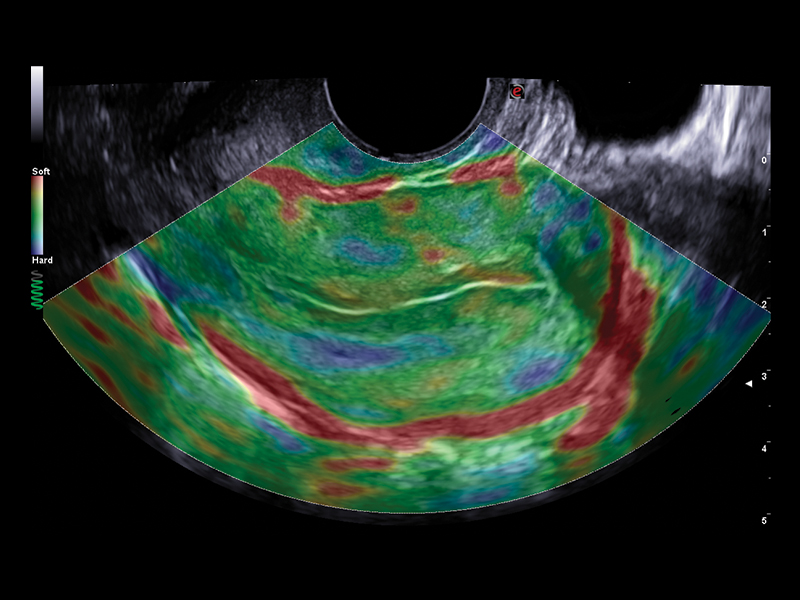

By associating various chromatic patterns, Esaote’s ElaXto strain technology offers real-time assessment of differing tissue response in terms of elasticity, to evaluate cervix elasticity for a proper embryo transfer.